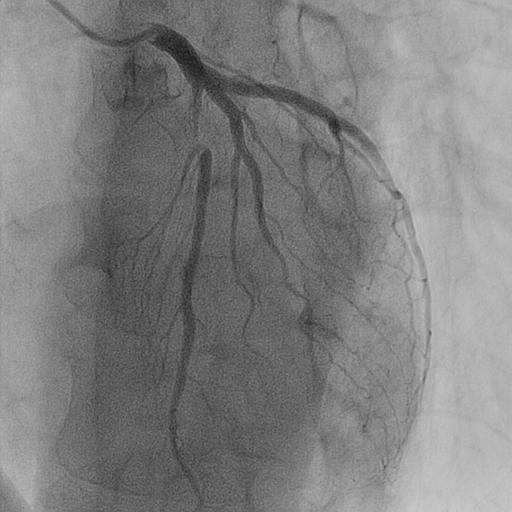

Relevant Catheterization Findings

Coronary angiography confirmed a hemodynamically significant stenosis in the mid-LAD, consistent with CCTA. OFDI revealed a high-intensity, heterogeneous signal with layered structure and microchannel formation, features suggestive of an organized thrombus rather than a lipid-rich atherosclerotic plaque. This morphology was considered to be associated with a low risk of plaque restenosis and favorable balloon response, making a stent-free strategy a reasonable therapeutic option.